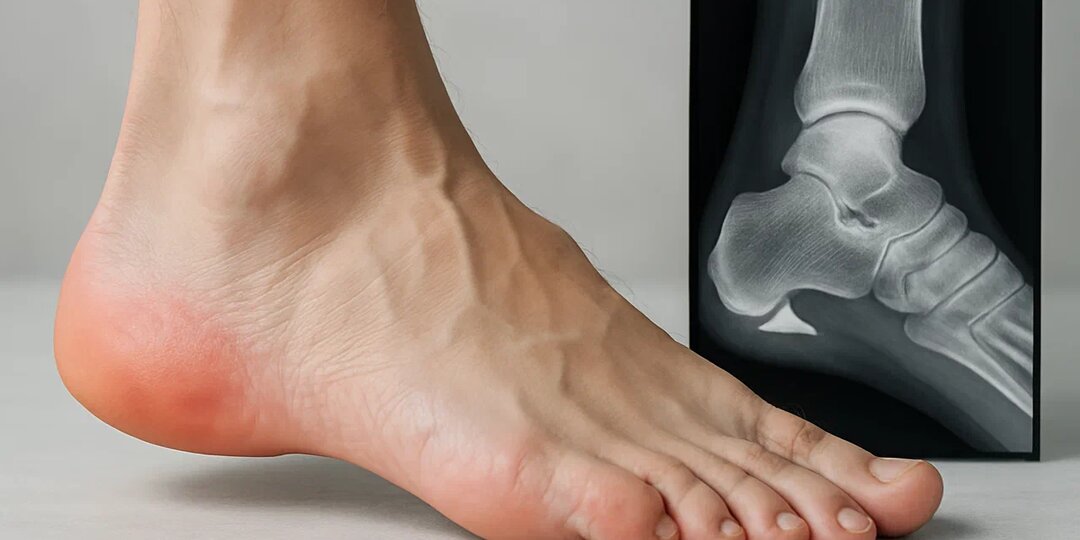

Откуда берётся пяточная шпора и как вернуть себе лёгкость шага

Представьте: вы встаёте утром с кровати, делаете первый шаг — и резкая, жгучая боль пронзает пятку, будто в неё вонзили раскалённый гвоздь. С каждым шагом всё хуже: невозможно ступить на пятку, приходится перекатываться на носок или хромать. Эта боль может пройти к обеду… но завтра утром вернётся вновь. Так начинается пяточная шпора — состояние, с которым сталкиваются миллионы людей, особенно после 40 лет. Многие думают, что шпора — это костный «нарост», который «врастает» в мягкие ткани и вызывает боль. Но на самом деле всё сложнее — и одновременно проще. Боль возникает не из-за самой шпоры, а из-за воспаления, которое её сопровождает. А значит — с ней можно справиться. Даже без операции. Давайте разберёмся, что на самом деле происходит в пятке, почему это случается именно с вами, и какие проверенные методы помогают вернуть лёгкость шага — без боли, без страха и без лишних расходов. Что такое пяточная шпора — на самом деле? Пяточная шпора — это кальциевое уплотнение (остеофит), кото